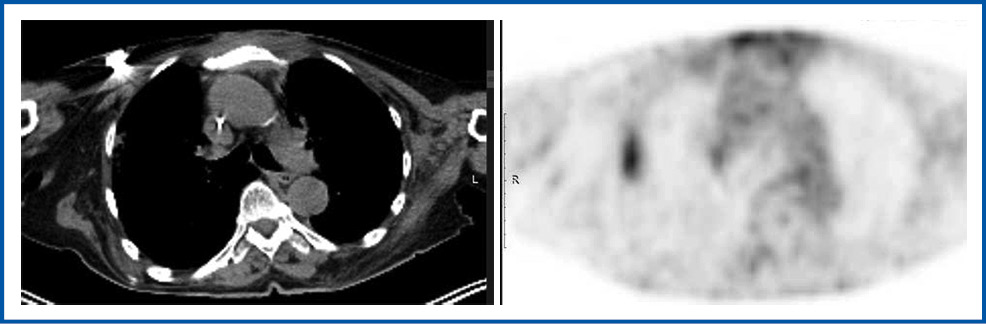

Однако с ноября 2022 г. – через 4 мес после начала таргетной терапии олапарибом – вновь отмечена отрицательная динамика в виде появления новых очагов: 7 очагов от 3 до 8 мм в мягких тканях передней грудной стенки в зоне прямой мышцы живота слева, подмышечной области справа до 20 мм, SUVmax 31 (рис. 6).

Рис. 6. Метастатический лимфатический узел в правой аксиллярной области по данным ПЭТ-КТ от ноября 2022 г.

Fig. 6. Metastatic lymph node in the right axillary region according to PET-CT dated November 2022.

Через 3 мес после завершения ЛТ зафиксирована выраженная положительная динамика в виде уменьшения размера метастатически измененного аксиллярного лимфатического узла справа до 6 мм (ранее 20 мм), с накоплением 18F-ФДГ SUVmax 1,86 (ранее 31,29).

Через 2 мес после проведенного лечения у пациентки определялось прогрессирование заболевания: появление новых очагов и увеличение ранее определявшихся очагов в мягких тканях передней грудной стенки ниже границы проведенной ранее ЛТ максимальным размером до 20 мм (ранее 3–8 мм) с накоплением 18F-ФДГ SUVmax 27,01 (ранее 12,22), увеличение прекардиальных лимфоузлов до 11 мм (ранее 7 мм) с накоплением 18F-ФДГ SUVmax 27,80 (ранее 23,42), увеличение образования в области прямой мышцы живота слева до 17×15 мм (ранее 4 мм), с накоплением 18F-ФДГ SUVmax 16,63 (ранее 4,17); рис. 8.

Рис. 8. ПЭТ-КТ от 07.03.2023, через 3 мес после завершения ЛТ, полная регрессия метастатического лимфатического узла в правой аксиллярной области.

Fig. 8. PET-CT dated 07.03.2023, 3 months after completion of RT; complete regression of the metastatic lymph node in the right axillary region.